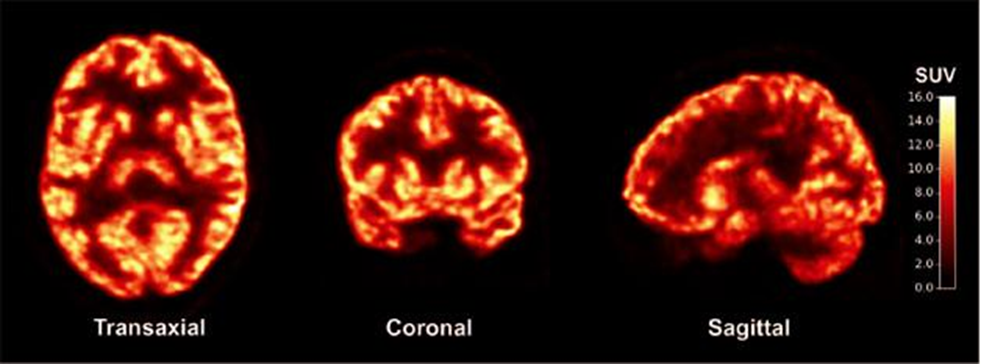

this image is an example of

F-18 FDG brain

what view is this image

transverse or axial

top to bottom

coronal

front to back

sagittal side to side